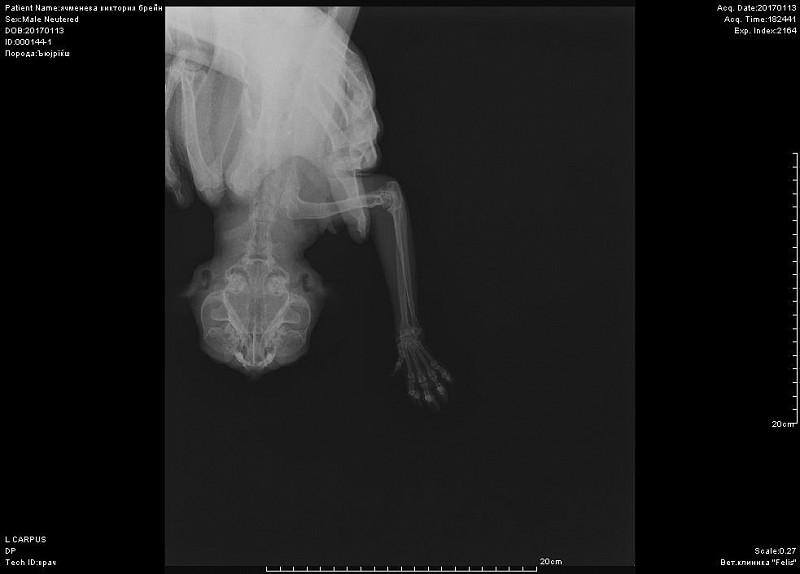

Периодически хромает после долгого лежания.Около 10 дней хромота не прошла, стал не наступать на переднюю лапу-ходит на трех. Повели в к врачу, при осмотре спокоен. Сделали снимок-врач сказал, что был когда-то компрессионный перелом лучевой кости, сказал, что кот хоить нормально больше не будет. Нужно еще мнение, посмотрите снимок, пожалуйста.

Добрый день! не вижу перелома на этом снимке. Нужна еще прямая проекция. Боль именно в запястном суставе?

К сожалению не знаем, где болит-реакции на пальпацию и энергичные движения в суставах не выявили. Именно на этом снимке врач мне указал на компрессию кости-как он сказал кость посередине должна быть квадратная, а она стала треугольной... Я сама нашла атлас посмотрела, что это нормальный вид лучевой кости.

Может быть Вы видите что-то не то на этом снимке? Может сустав? Мы были у другого врача, он снимки читать не может, сказал, что вроде не видит перелома, но точно сказать не может- предположил заболевание сустава-уколы нестероидные, кальций и пьем страйт глюкозамин с хндроитином. Второй врач зафиксировал лангеткой ногу коту. Других снимков не записали, хотя я видела в прямой проекции.

вот такой снимок целиком-первое фото-это я увеличила, может быть другие суставы на этой лапе Вы тоже посмотрите. А также, пожалуйста, порекомендуйте кому можно показать кота в спб, может Вы знаете.

Вот снимок, посмотрите, пожалуйста.

По-прежнему не вижу перелома, но последнее изображение увеличить не могу.

вот в запястном суставе не вижу изменений.А вот локтевом есть признаки артроза. Но все же это не прямая и даже не боковая проекция локтя.